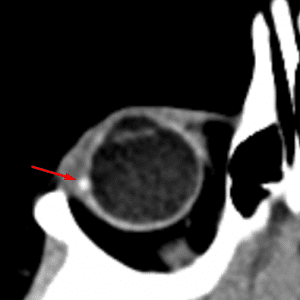

Optic Disc Drusen

Mimicking a foreign body or mass